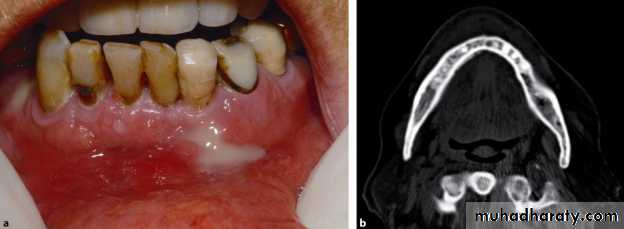

Fibrous dysplasia of left maxilla with involvement of both labial as well as palatal surface with visible left palatal bulge

Buccal exostoses: Multiple bony nodular excrescences (growth) in the buccal aspect of .the maxilla

Facial asymmetry with apparent massive swelling involving the right side of the lower jaw measuring approx. 6.8 * 7.2 cm. The swelling was firm and non tender

Huge soft tissue mass obliterating the buccal, as well as the lingual sulcus pushing the tongue to the contra lateral side. The superior surface of the mass was ulcerated and eroded.

Dgx: Aneurysmal bone cyst of the mandible